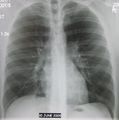

A chest X-ray showing a very prominent wedge shaped pneumonia in the right lung. | |